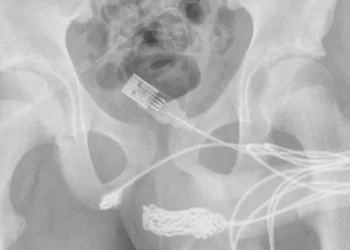

Un adolescente, de 15 años, estaba tratando de medir el interior de su pene con el cable USB como una ...